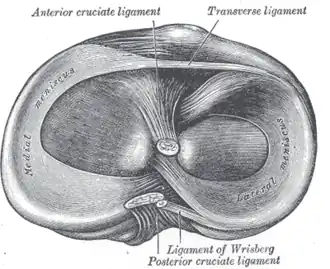

Na anatomia, os meniscos são cartilagens presentes na articulação tíbiofemoral (região do joelho), entre os côndilos do fêmur e da tíbia. Os meniscos têm a função de diminuir o impacto e promover a adaptação (melhorar o encaixe) entre as faces articulares do fêmur e da tíbia.[1] Melhoram a congruência das superfícies articulares[2], além de dar mais mobilidade, lubrificação ao joelho.[3]

São dois meniscos, um medial e outro lateral, ambos localizados acima da tíbia. Têm o formato de meia lua, com uma divisão em corno anterior, corpo e corno posterior. Como cartilagem, apresentam poucos vasos sangüíneos, o que dificulta sua capacidade de regeneração, caso sofram alguma lesão. Uma vez lesionados, dificilmente se recuperam espontaneamente.

Os cornos dos meniscos possuem distancias, sendo que os do externo estão mais próximos entre si que os internos. E não estão livres no espaço articulares, mantendo uma junção funcional.[4]